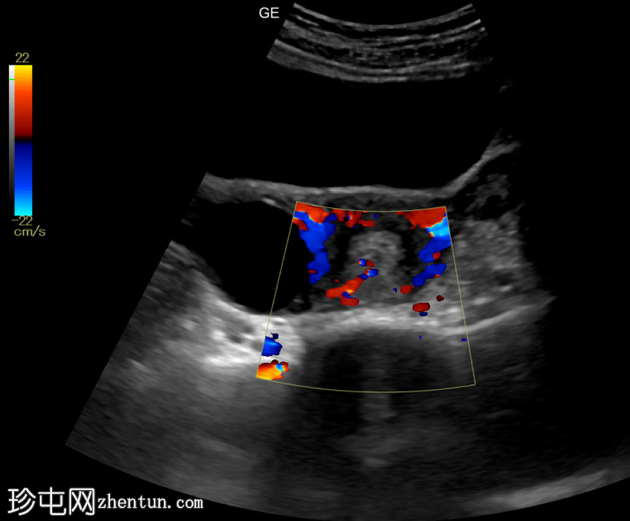

超声

检查

纵切面

横切面

子宫内膜腔内可见边界清晰的高回声病灶,大小为36 x 20 x 21mm,彩色多普勒显示其周围有供血动脉。

子宫内膜腔内可见高回声病灶,并有供血动脉,这是超声检查中子宫内膜息肉的典型特征。患者持续阴道出血一个月。